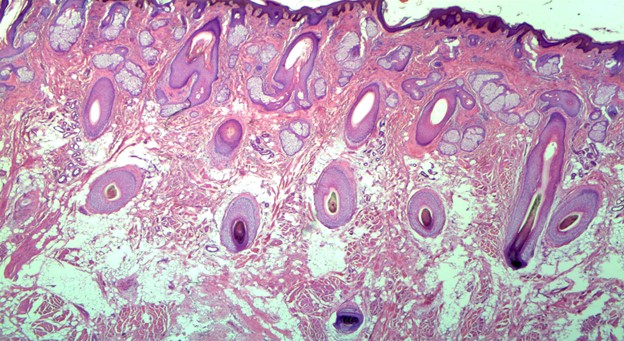

Histopathology of the specimen was notable for abundant haphazard bundles of mature striated muscle admixed with adipose tissue, sclerotic collagen bundles, nerve bundles, and prominent folliculosebaceous adnexa within the reticular dermis and subcutaneous tissue (Figures 1, 2). There was no evidence of cystic elements or malignancy on histopathologic evaluation. Thus, the histopathologic findings were consistent with a diagnosis of RMH.

Figure 1: Hematoxylin & Eosin Stain displaying abundant haphazard bundles of mature striated muscle admixed with adipose tissue, sclerotic collagen bundles, nerve bundles, and prominent folliculosebaceous adnexa within the reticular dermis and subcutaneous tissue (20x).